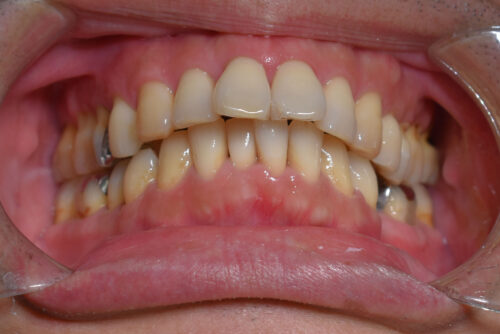

初診時年齢 39歳 男性

歯のでこぼこ(叢生)

下顎左側第二小臼歯欠損

出っ歯

本症例も

上下とも歯が唇側に傾斜し

出っ歯も呈しておりました。

ワイヤー9か月後です。